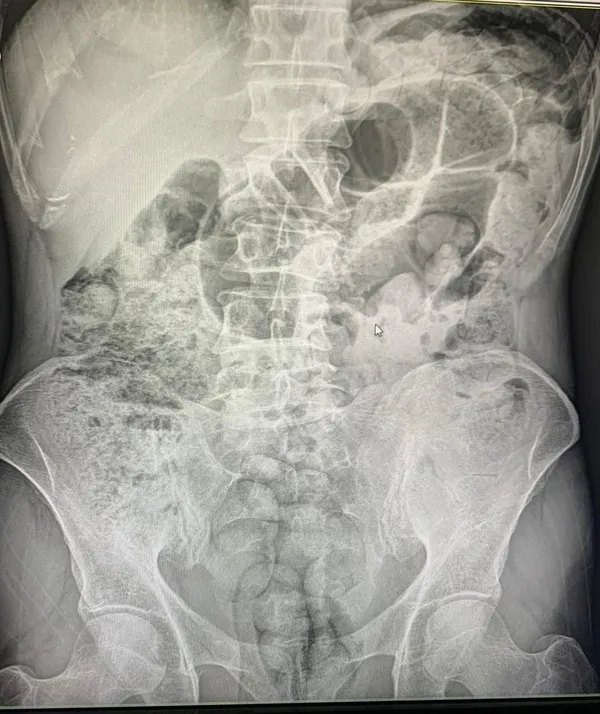

Sağlık ekipleri gözetiminde hastaneye sevk edilen şüpheliler, yaklaşık 10 gün süren tıbbi takip ve tedavi sürecinin ardından ameliyata alındı. Cerrahi müdahaleler sonucunda şüphelilerin midelerinden 119 paket halinde toplam 1 kilo 597 gram uyuşturucu madde çıkarıldı. Gözaltına alınan zanlılar, emniyetteki işlemlerinin tamamlanmasının ardından sevk edildikleri adli makamlarca tutuklanarak cezaevine gönderildi. Siirt Emniyet Müdürlüğü yetkilileri, uyuşturucu ticareti ve sevkiyatına karşı mücadelenin aralıksız ve kararlılıkla sürdürüleceğini vurguladı.